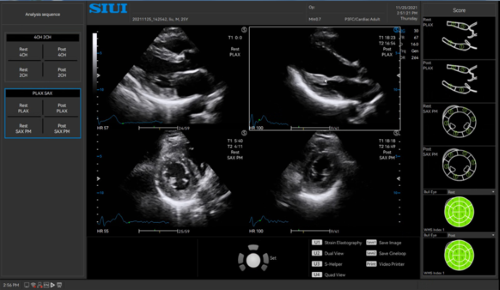

· Stress Echo assists in evaluating how coronary arteries respond to the stress by comparing myocardial motion at rest and under stress.